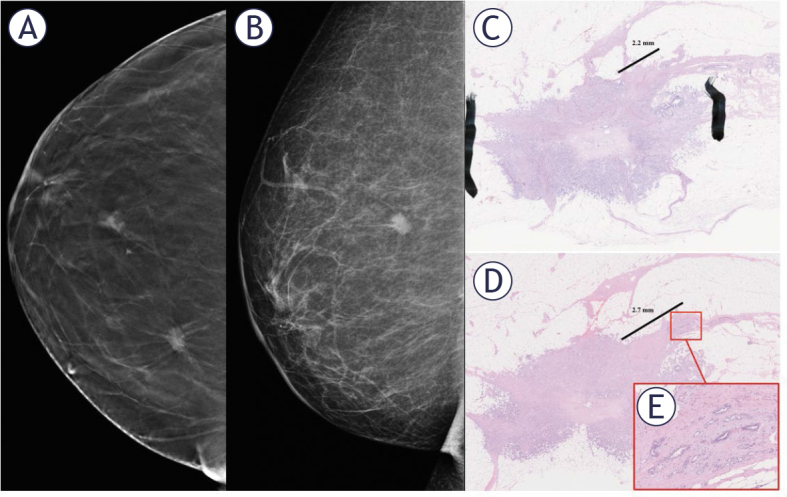

背景:在影像学上,乳腺恶性肿块通常伴有针状体。据我们所知,这种针状体的临床意义以前还没有研究过,也没有针对乳房x光检查发现的针状体的手术指南。患者和方法:2018年4月至2019年12月期间,回顾性分析所有连续行保乳手术的浸润性恶性病变患者,这些患者需要术中乳房放射标本评估并进行断层合成。肿瘤分为两组:以毛刺边缘为主要特征的肿瘤和具有其他明显形态特征的肿瘤。通过术前和术中影像学评估两组针状体的可视化、长度和分布,并与针状体的组织病理学特征进行比较。结果:共评估162个浸润性病变。存在针状体相关的附加肿瘤灶是一种常见的发现;67.6%的针状肿瘤和48.9%的其他肿瘤有附加灶。大多数附加病灶位于肿瘤边缘1cm以内。从主要肿瘤边缘到针状体相关的附加肿瘤病灶的平均病理测量距离为4.3±2.8 mm。与术中图像测得的最大针尖长度(9.5±5.1 mm)相比,实际肿瘤浸润的距离要短得多,相关性很弱。结论:乳腺肿瘤针状体有额外的肿瘤灶,可能导致边缘阳性,有再次手术的可能。需要进一步的研究来确定针状体的实际肿瘤负荷和临床意义。

Results: In total, 162 invasive lesions were evaluated. The presence of spicule-associated additional tumor foci was a common finding; 67.6% of the spiculated tumors and 48.9% of the other tumors had additional foci. Most additional tumor foci were within 1 cm of the tumor edge. The mean pathologically measured distance from the main tumor margin to the spicule-associated additional tumor foci was 4.3 ± 2.8 mm. Compared to the maximum spicule length determined from intraoperative images (9.5 ± 5.1 mm), the distance of actual tumor infiltration was much shorter, and a very weak correlation was observed.